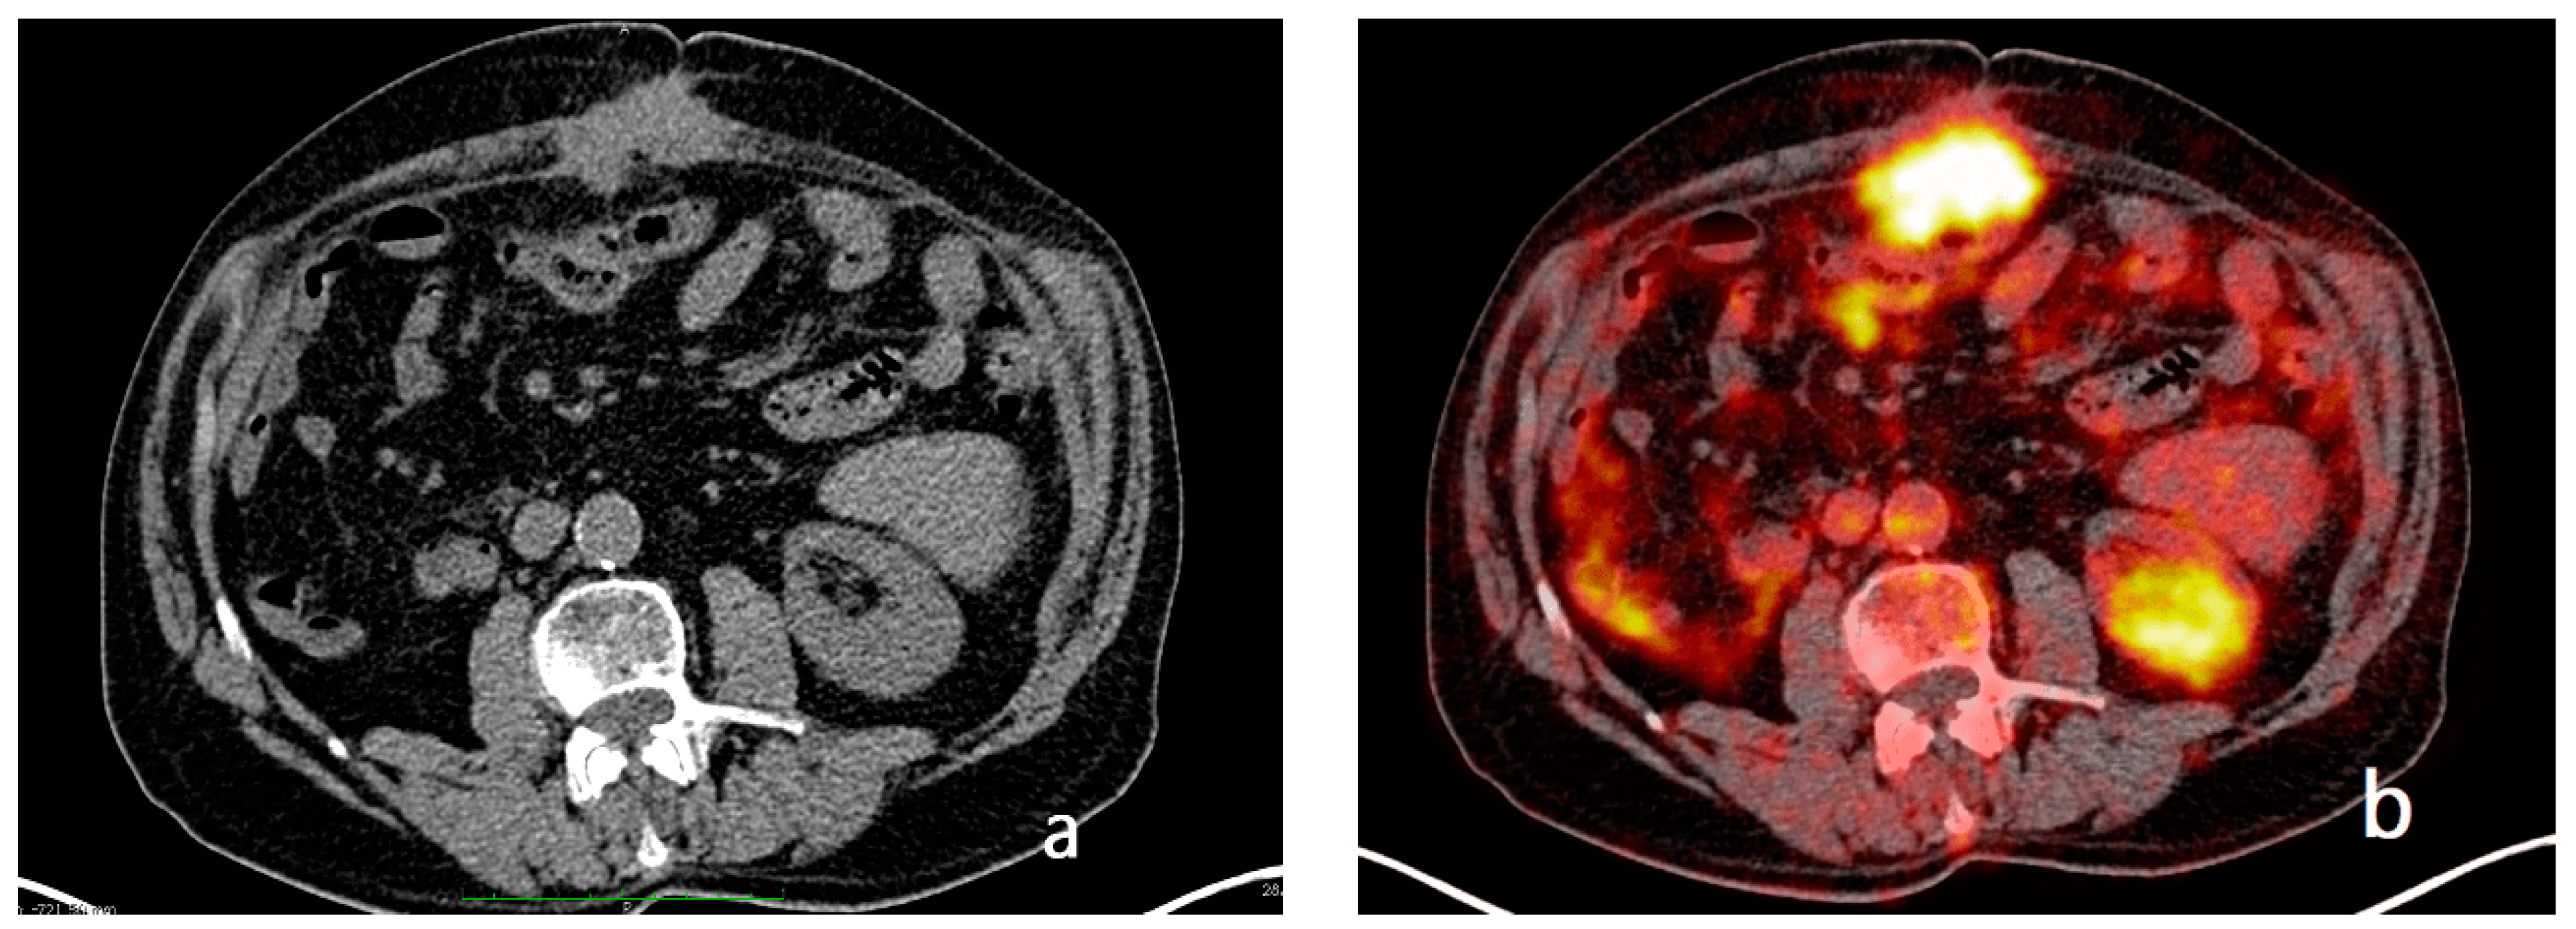

- Mesenteral root involvementDisease in the small bowel and intestinal mesentery constitutes a sentinel and limiting criterion in decision making in CRS. Therefore, the evaluation of small-bowel loops and their mesentery should be a key component in the preoperative imaging evaluation of a patient with PC [24]. The diffuse involvement of the mesentery root is, in fact, a criterion for unresectability. Thin mesenteral tumor sheets are invisible on CT and PET scans [111]. In a study of 30 cases by Dromain et al. [87], CT detected implants in the small bowel in 26% of cases, whereas the true incidence of this disease location at the time of surgery was 83%.Furthermore, MRI has been reported to be superior to CT in the evaluation of the intestinal tract and mesenteric involvement in light of its high capacity in soft-tissue studies [112].Diffuse small-bowel involvement (mesentery and/or intestinal serosa) remains difficult to represent, however, and when present, the radiologist should estimate the extent of involvement as less than or greater than 50%. The radiologist should also describe the number and location of any stenosis of segments of the small intestine, as well as invasion of the colon or gastric system, to produce a complete analysis of the entire digestive tract [69].Indeed, Jacquet et al. [43] found that when preoperative CT showed a tumor causing intestinal obstruction, surgical cytoreduction was suboptimal in 88% of cases. If the tumor obstructing the jejunum or superior ileum was greater than 5 cm in diameter, no subject had a complete CRS.In fact, the two radiologic findings that Sugarbaker et al. [113] reported as most strongly associated with poor outcomes in CRS are the presence of tumor nodules greater than 5 cm on small-bowel surfaces and segmental small-bowel obstruction.Preoperative imaging can aid in patient selection by avoiding surgery for patients whose tumors are excessively large for adequate surgical cytoreduction; in particular MRI using gadolinium and DWI sequences routinely describe tumor-cell sheets involving the serosa of the small intestine and mesentery, which are typically not seen on CT or PET [55] (Figure 14 and Figure 15).